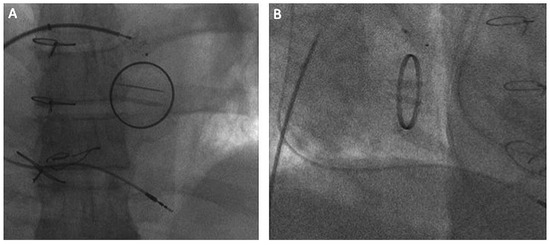

Waiting for Evidence Seems to Make Sense—Except for the One Providing the Evidence

by Thomas Pilgrim, Rolf Vogel and Bernhard Meier

A 58-year-old male presented with a history of two prior transient ischaemic attacks and was found to have a patent foramen ovale (PFO) in the absence of atrial fibrillation or relevant carotid atheromatosis. PFO closure was deferred at this stage due to the [...] Read more.

A 58-year-old male presented with a history of two prior transient ischaemic attacks and was found to have a patent foramen ovale (PFO) in the absence of atrial fibrillation or relevant carotid atheromatosis. PFO closure was deferred at this stage due to the lack of clinical evidence. Three years later the patient was re-admitted after a major stroke with residual symptoms and finally underwent PFO closure in a minimally invasive procedure using an Amplatzer PFO Occluder. Full article

Show Figures

Figure 1